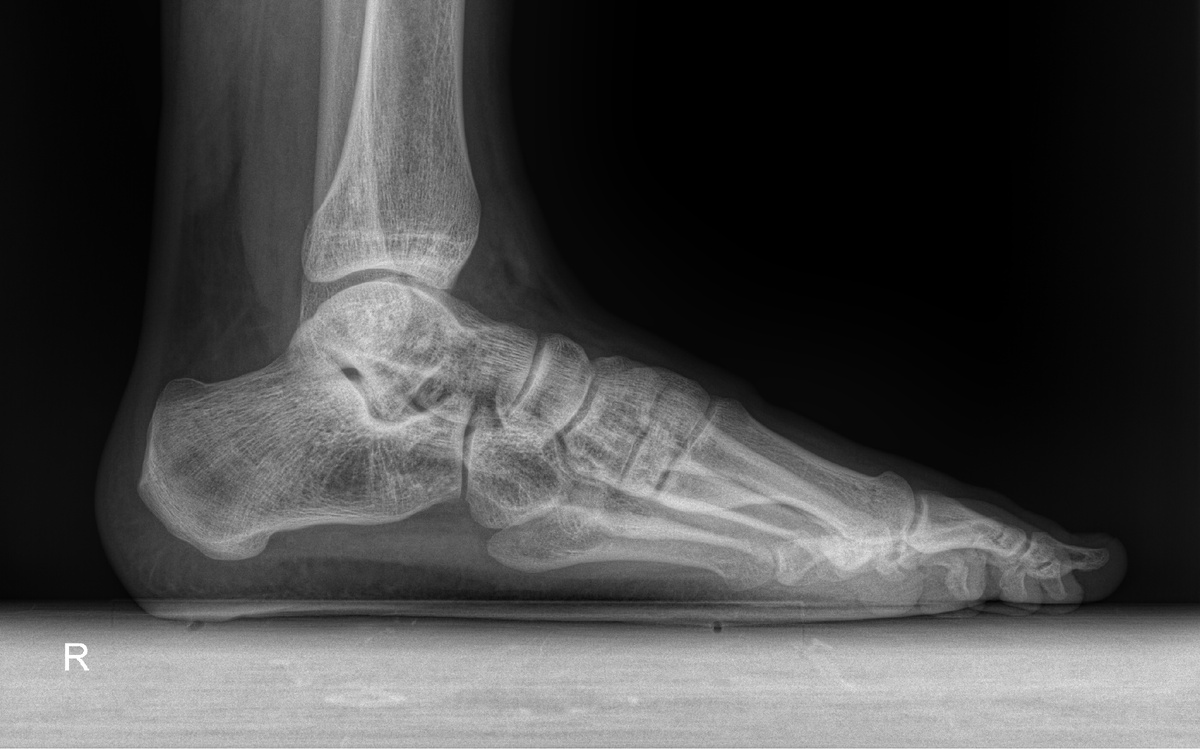

Рентгенограмма правой стопы в двух проектциях